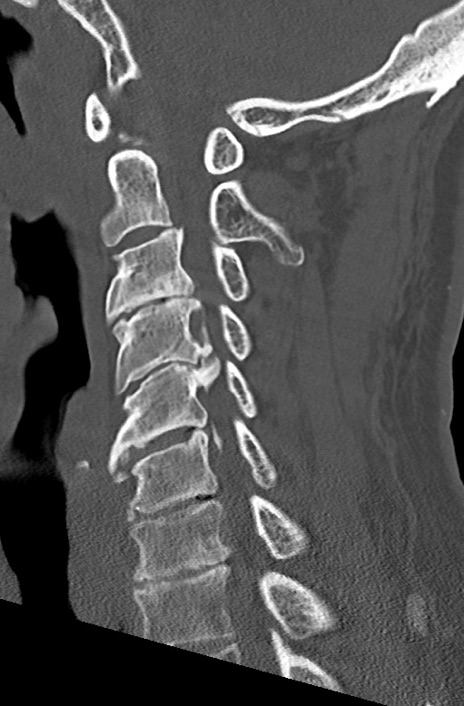

頚椎CT

冠状断像

矢状断像と横断像